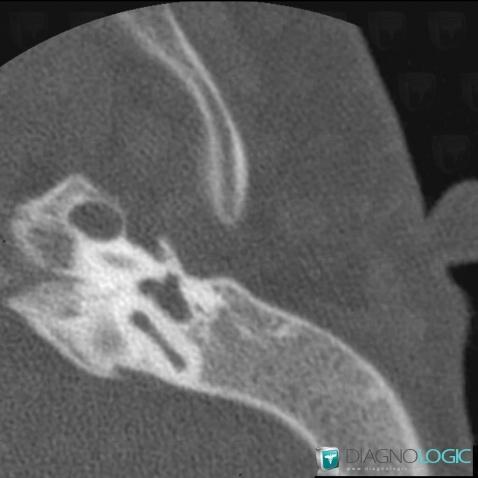

- Diagnosis Major aplasia, Location(s) Middle ear, with gamuts External ear, with gamuts External ear lesion